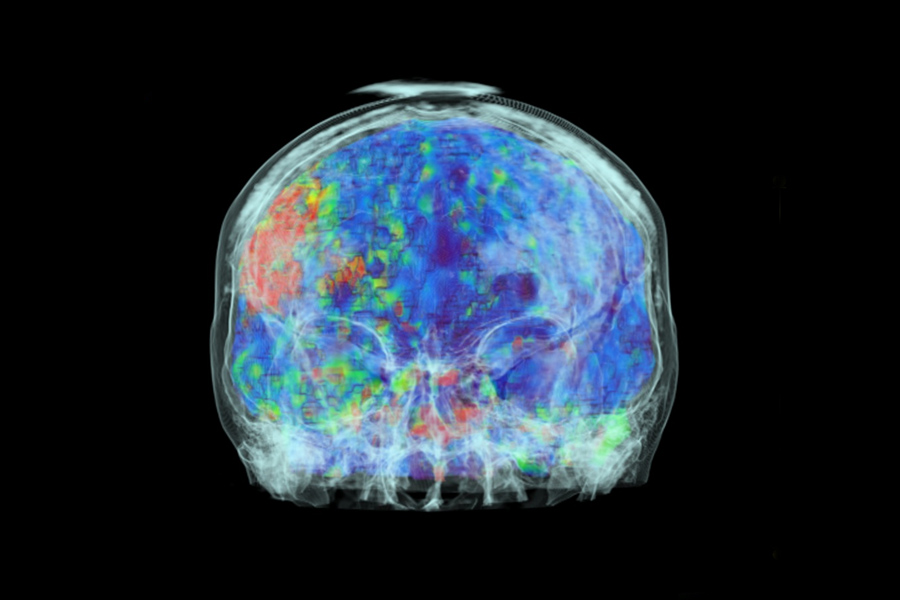

Im Klinikum steht rund um die Uhr eine CT-Versorgung zur Verfügung. Wir betreiben ein Volumen-CT (320 Zeilen) der neuesten Generation. Durch seinen besonders breiten Detektor (16 cm) sind sehr kurze Untersuchungszeiten möglich. Dieses Gerät kann Aufnahmen einzelner Gelenke oder ganzer Organe in nur einer Umdrehung erzeugen. Dies führt zu einer deutlich verbesserten zeitlichen und örtlichen Bildauflösung, was insbesondere für die Durchblutungsmessung des Gehirns oder die Herzbildgebung von entscheidendem Vorteil ist.

- Darstellung des Schädels